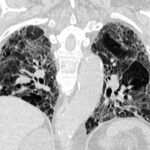

Immagine: Credit: Public Domain.

Le metastasi cerebrali vengono diagnosticate ogni anno a circa 200.000 pazienti affetti da cancro, ma esistono poche opzioni di trattamento perché i meccanismi che consentono al cancro di diffondersi al cervello rimangono poco chiari. Tuttavia, uno studio recentemente pubblicato sulla rivista Cancer Cell dallo scienziato del VCU Massey Cancer Center Suyun Huang, MD, Ph.D., offre speranza per lo sviluppo di terapie future mostrando come un gene poco conosciuto noto come YTHDF3 svolga un ruolo significativo nel processo.